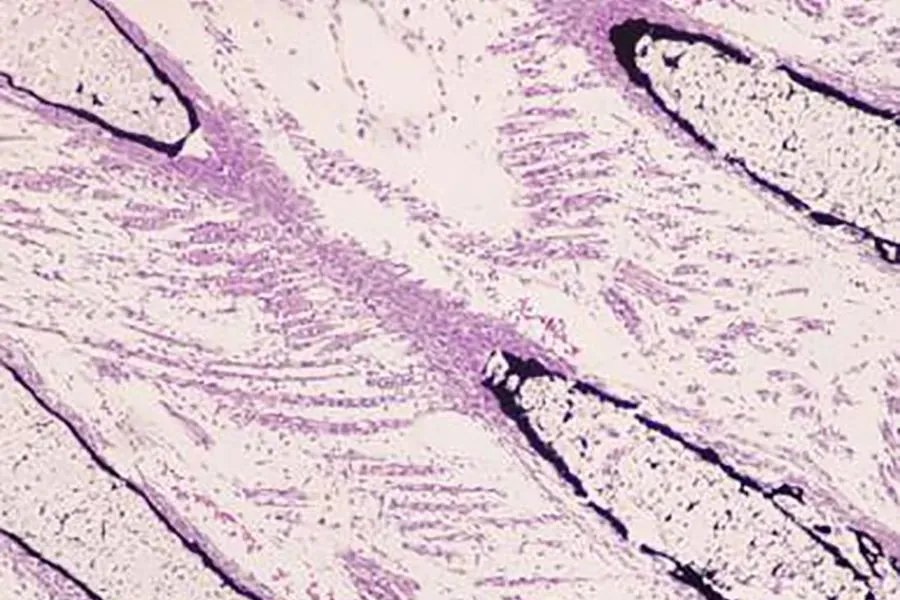

图片

Masson三色染色试剂盒-正常小鼠肾组织